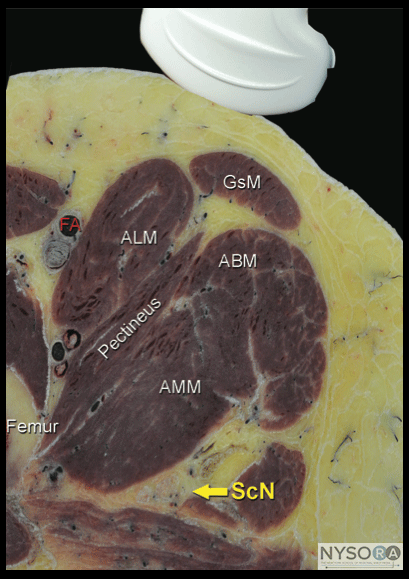

PART 1: ANTERIOR APPROACH ![]() Figure 1-2: Cross-sectional anatomy of the sciatic nerve (ScN). Shown are femoral artery (FA), adductor longus muscle (ALM), pectineus muscle, adductor magnus muscle (AMM), adductor brevis muscle (ABM), gracilis muscle (GsM), and the femur. The sciatic nerve is seen posterior to the AMM.

Figure 1-3: Ultrasound anatomy of the sciatic nerve. From superficial to deep; femoral artery (FA) and femur laterally, adductor magnus muscle (AMM) and sciatic nerve (ScN) laterally. The sciatic nerve is typically located at a depth of 6 to 8cm. General Considerations The anterior approach to sciatic block can be useful in patients who cannot be positioned in the lateral position due to pain, trauma, presence of external fixation devices interfering with positioning, and other issues. It also may be well-suited to patients who require postoperative blocks for analgesia following a total knee arthroplasty. Ultrasonography adds the benefit of no requirement for the palpation of a femoral pulse or the use of geometry for identification of the skin puncture point. In addition, using the ultrasound-guided approach should reduce the risk of puncture of the femoral artery as compared with the landmark-based approach. The actual scanning and needle insertion are performed on the anteromedial aspect of the proximal thigh, rather than the anterior surface, and may require a slight abduction and external rotation of the thigh. This block is not well suited to insertion of catheters because a large needle must traverse several muscles (causing pain and possibly hematomas), an awkward catheter location (medial thigh), and catheter insertion at approximately perpendicular angle to the sciatic nerve is difficult. Ultrasound Anatomy The sciatic nerve is imaged approximately at the level of the minor trochanter. At this location, a curved transducer placed over the anteromedial aspect of the thigh will reveal the musculature of all three fascial compartments of the thigh: anterior, medial, and posterior (Figures 1-2 and 1-3). Beneath the superficial sartorius muscle is the femoral artery, and deep and medial to this vessel is the profunda femoris artery. Both of these can be identified with color Doppler ultrasound for orientation. The femur is easily seen as a hyperechoic rim with the corresponding shadow beneath the vastus intermedius. Medial to the femur is the body of the adductor magnus muscle, separated by the fascial plane(s) of the hamstrings muscles. The sciatic nerve is visualized as a hyperechoic, slightly flattened oval structure sandwiched between these two muscle planes. The nerve is typically visualized at a depth of 6 to 8 cm (Figure 1-3). ![]() Figure 1-4: Transducer position to visualize the sciatic nerve through the anterior approach. Distribution of Blockade Sciatic nerve block results in anesthesia of the posterior aspect of the knee, hamstrings muscles, and entire lower limb below the knee, both motor and sensory, with the exception of skin on the medial leg and foot (saphenous nerve). The skin of the posterior aspect of the thigh is supplied by the posterior cutaneous nerve of the thigh, which has its origin from the sciatic nerve more proximal than the anterior approach. It is, therefore, not blocked by the anterior approach. Practically, however, the lack of anesthesia in its distribution is of little clinical consequence. Equipment Equipment needed is as follows: